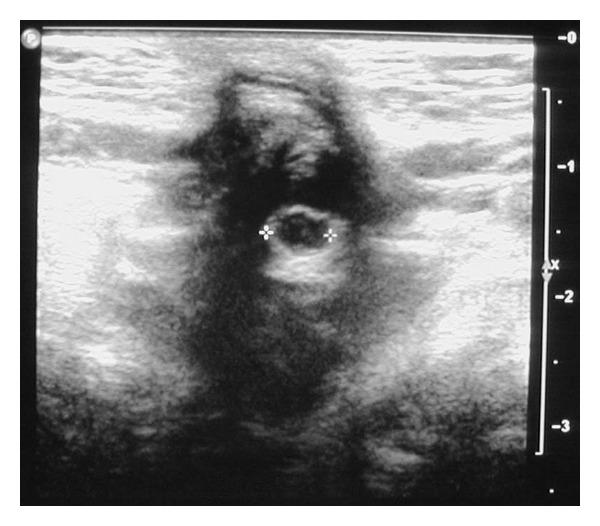

Umbilical discharge in infancy is often attributed to infection or an umbilical granuloma. It is important to investigate if such a discharge is due to an underlying congenital abnormality because corrective surgical intervention may then be required. We present the first case of an infant with a persistent umbilical discharge from an omphalomesenteric duct cyst. The discharge was associated with periumbilical dermatitis. The dermatitis was most likely due to irritation of the skin by gastric acid produced by the ectopic gastric mucosa contained in the omphalomesenteric duct cyst. Both discharge and dermatitis resolved after surgical removal of the cyst.

婴儿期的脐部渗液通常归因于感染或脐肉芽肿。重要的是要调查这种渗液是否源于潜在的先天性异常,因为可能需要进行矫正性手术干预。我们报告首例因卵黄管囊肿导致持续性脐部渗液的婴儿病例。渗液伴有脐周皮炎。皮炎很可能是由卵黄管囊肿内异位胃黏膜产生的胃酸刺激皮肤所致。手术切除囊肿后,渗液和皮炎均消失。